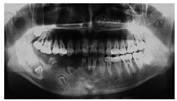

病例3:患者男性,15岁,因"右下颌恒牙未萌出"于2016年7月就诊于四川大学华西口腔医院正畸科。既往史及家族史无特殊。口内检查显示,右侧下颌区域无牙齿萌出,81滞留。曲面体层X线片示右侧下颌骨内见4颗埋伏阻生的异形牙胚,其中2颗低位,密度较正常牙低,硬组织层薄,牙釉质和牙本质界限不可辨认,髓腔宽大,根管粗,根尖孔敞开,呈"鬼影样"表现,阻生牙牙冠周围被囊性低密度影包绕,囊腔边界清楚,可见骨白线;81滞留;余颌骨未见明显异常(图3)。病变累及右下象限牙齿。诊断:牙列缺损及埋伏多生牙。随后于种植科、牙槽外科就诊。拔除滞留81与右下颌骨内埋伏阻生牙,半年后活动义齿修复,待患者成年后行种植义齿修复。